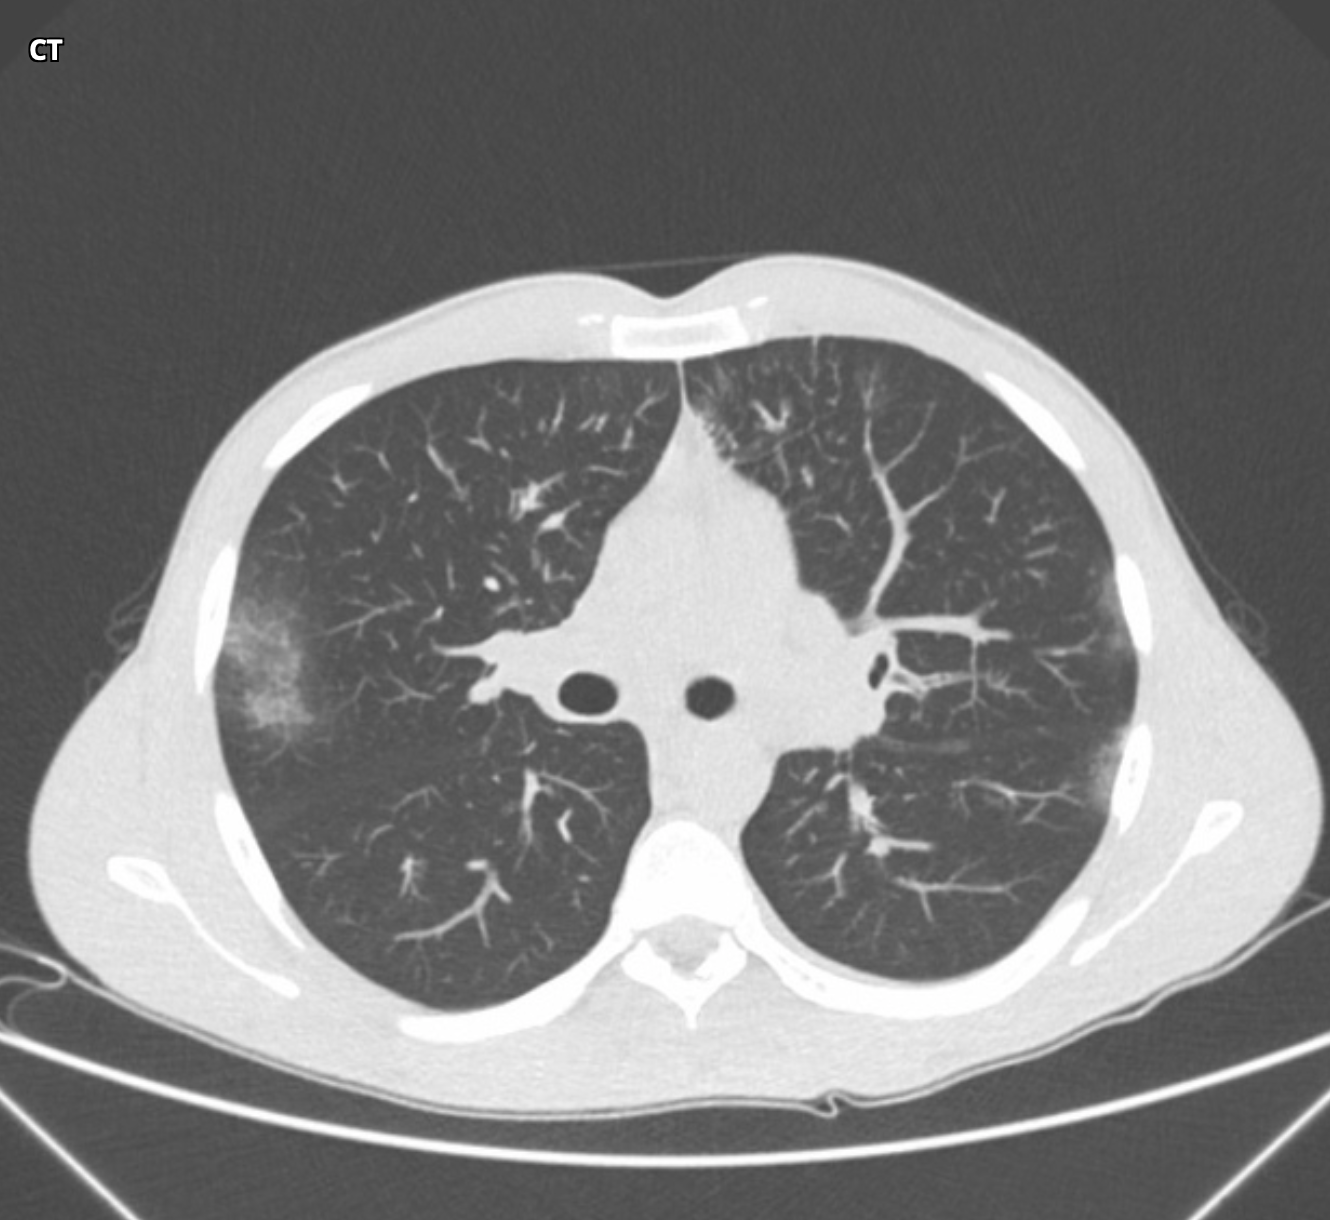

ACUTE INTERSTITAL PNEUMONIA

• Appears similar to ARDS but often with a symmetric Lower Lobe distribution

• EXUDATIVE PHASE (shown in pic one case)

• GGO

• Consolidation

• ORGANISING PHASE (pic two)

• architectural distortion

• traction bronchiectasis

• Honey combing